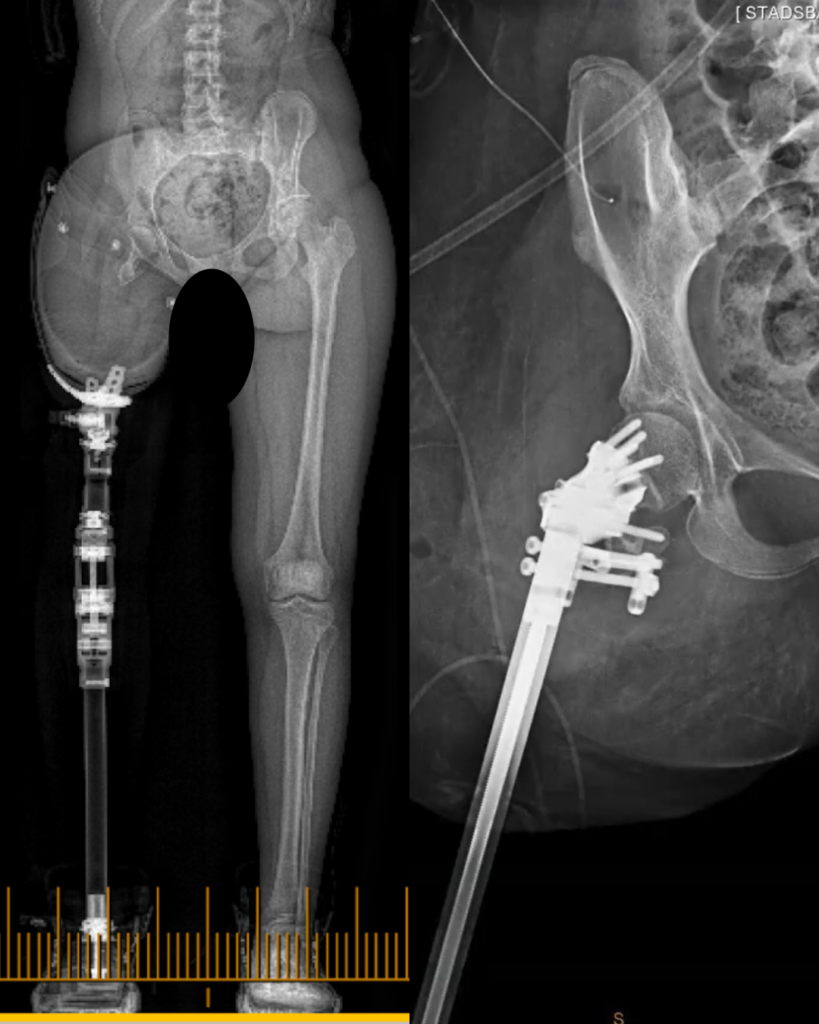

New study examines efficacy of Osseointegration in patients with Vascular Disease.

Peripheral vascular disease, or PVD, has traditionally been considered problematic for osseointegration due to concerns around impaired wound healing and the increased risk of post-operative